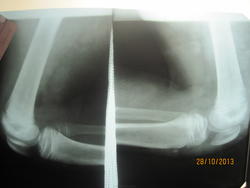

Всё узнала - болен в течении 1недели, жалобы на нарушение походки ( прихрамывание на левую ногу), Т37,2, умеренная болезненность при пальпации нижней части надколенника, и при сильном сгибании. Визуально симметричны = 32см, отечности и гиперемии нет. Узи левого коленного сустава- отечность мягких тканей, минимальное кол-во жидкости не требующее пункции. З-е: Косвенные узи признаки левостороннего артрита.

Такое ощущение, что бугристость болшеберцовой кости фрагментирована справа.

А на Осгуд-Шлаттера не тянет слева?